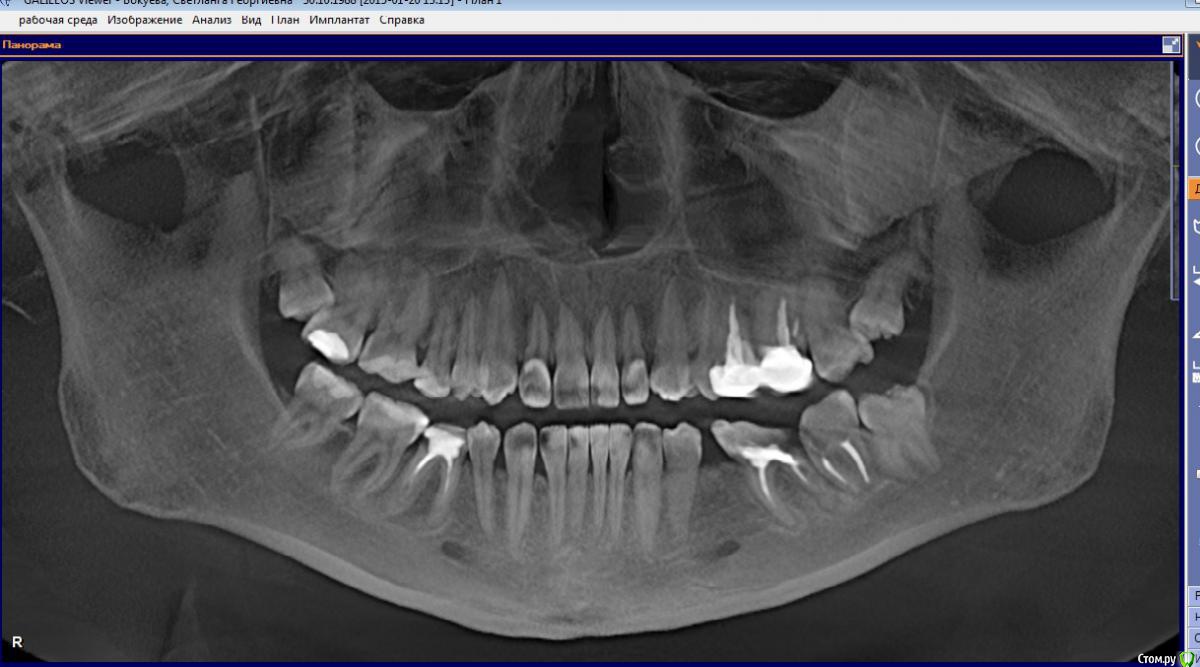

Margo03 Опубликовано 13 апреля, 2015 Поделиться Опубликовано 13 апреля, 2015 Добрый вечер! Интерисует вопрос , можно ли поставить коронку на 7 нижний зуб с левой стороны, если стенка зуба откололась в ровень с десной? Есть ли какие-то методы востановления зуба для дальнейшего протезирования? Или зуб только под удаление и имплант? На 6 -ку рядом точно не поставить , хотелось бы всё-таки один зуб сохранить на этой стороне. Заранее спасибо за ответ! Ссылка на комментарий

Гарриевич Опубликовано 13 апреля, 2015 Поделиться Опубликовано 13 апреля, 2015 (изменено) прицельный снимок нуженпредварительно по 7ке: можно нарежте пару срезов в области 7 зуба Изменено 13 апреля, 2015 пользователем Гарриевич Ссылка на комментарий

Vadim09 Опубликовано 13 апреля, 2015 Поделиться Опубликовано 13 апреля, 2015 К сожалению, по снимку нельзя увидеть язычную и щечную стороны, оценить, надо смотреть в кресле. Ссылка на комментарий